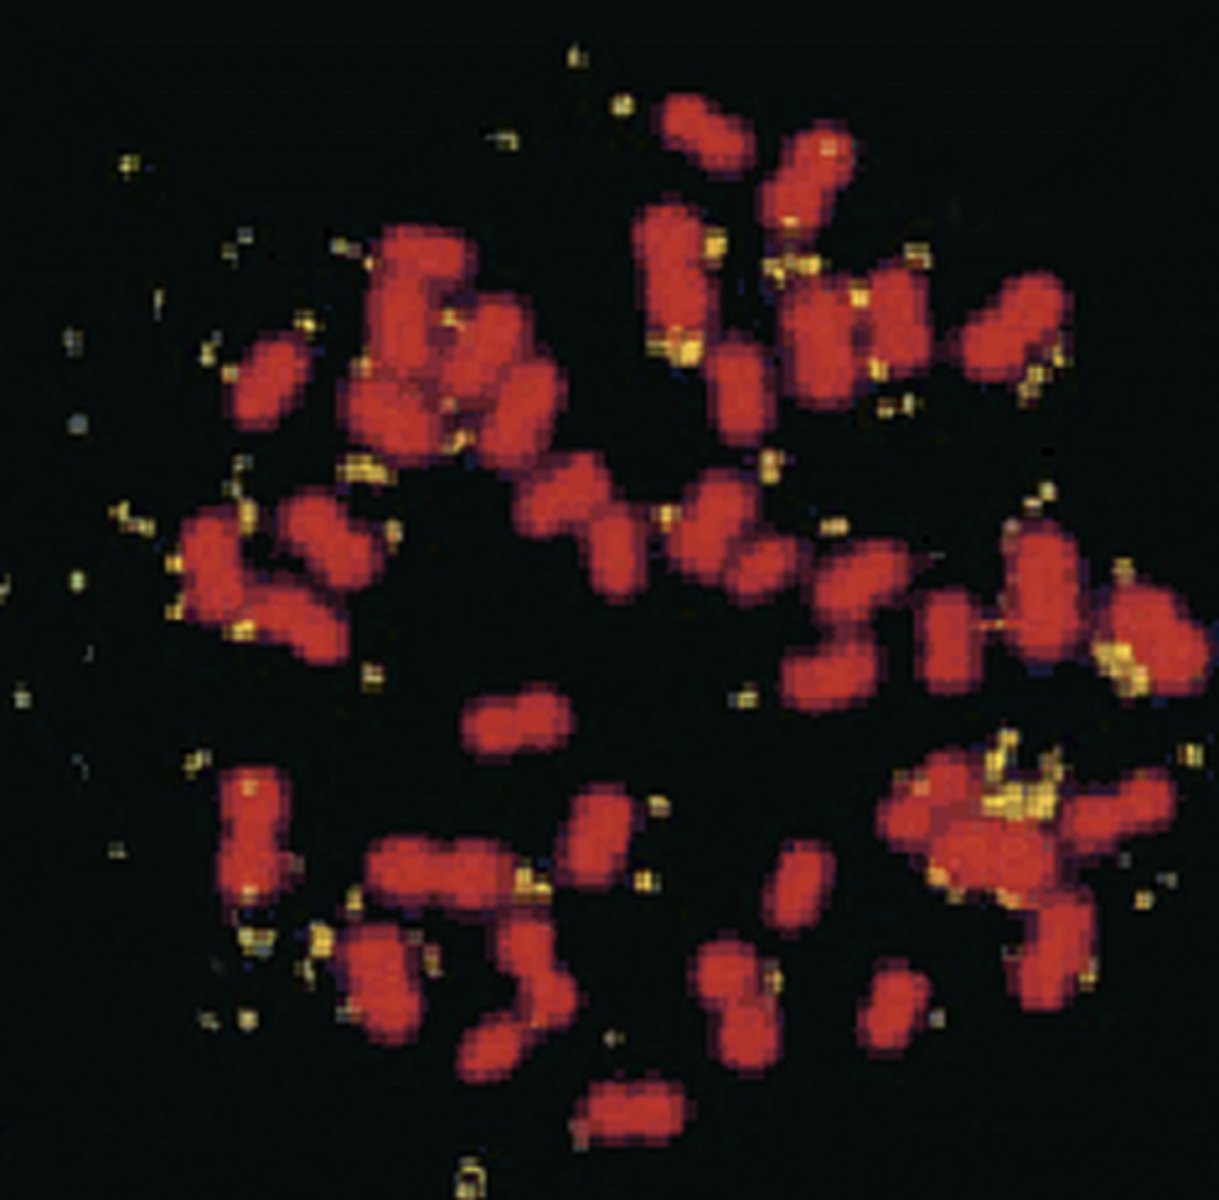

double minutes

extrachromosomal, autonomously replicating segments that were originally part of the chromosome

ex) breast cancer cells with amplified HER2/neu oncogene borne on DMs—causes a great increase in the dosage of that gene